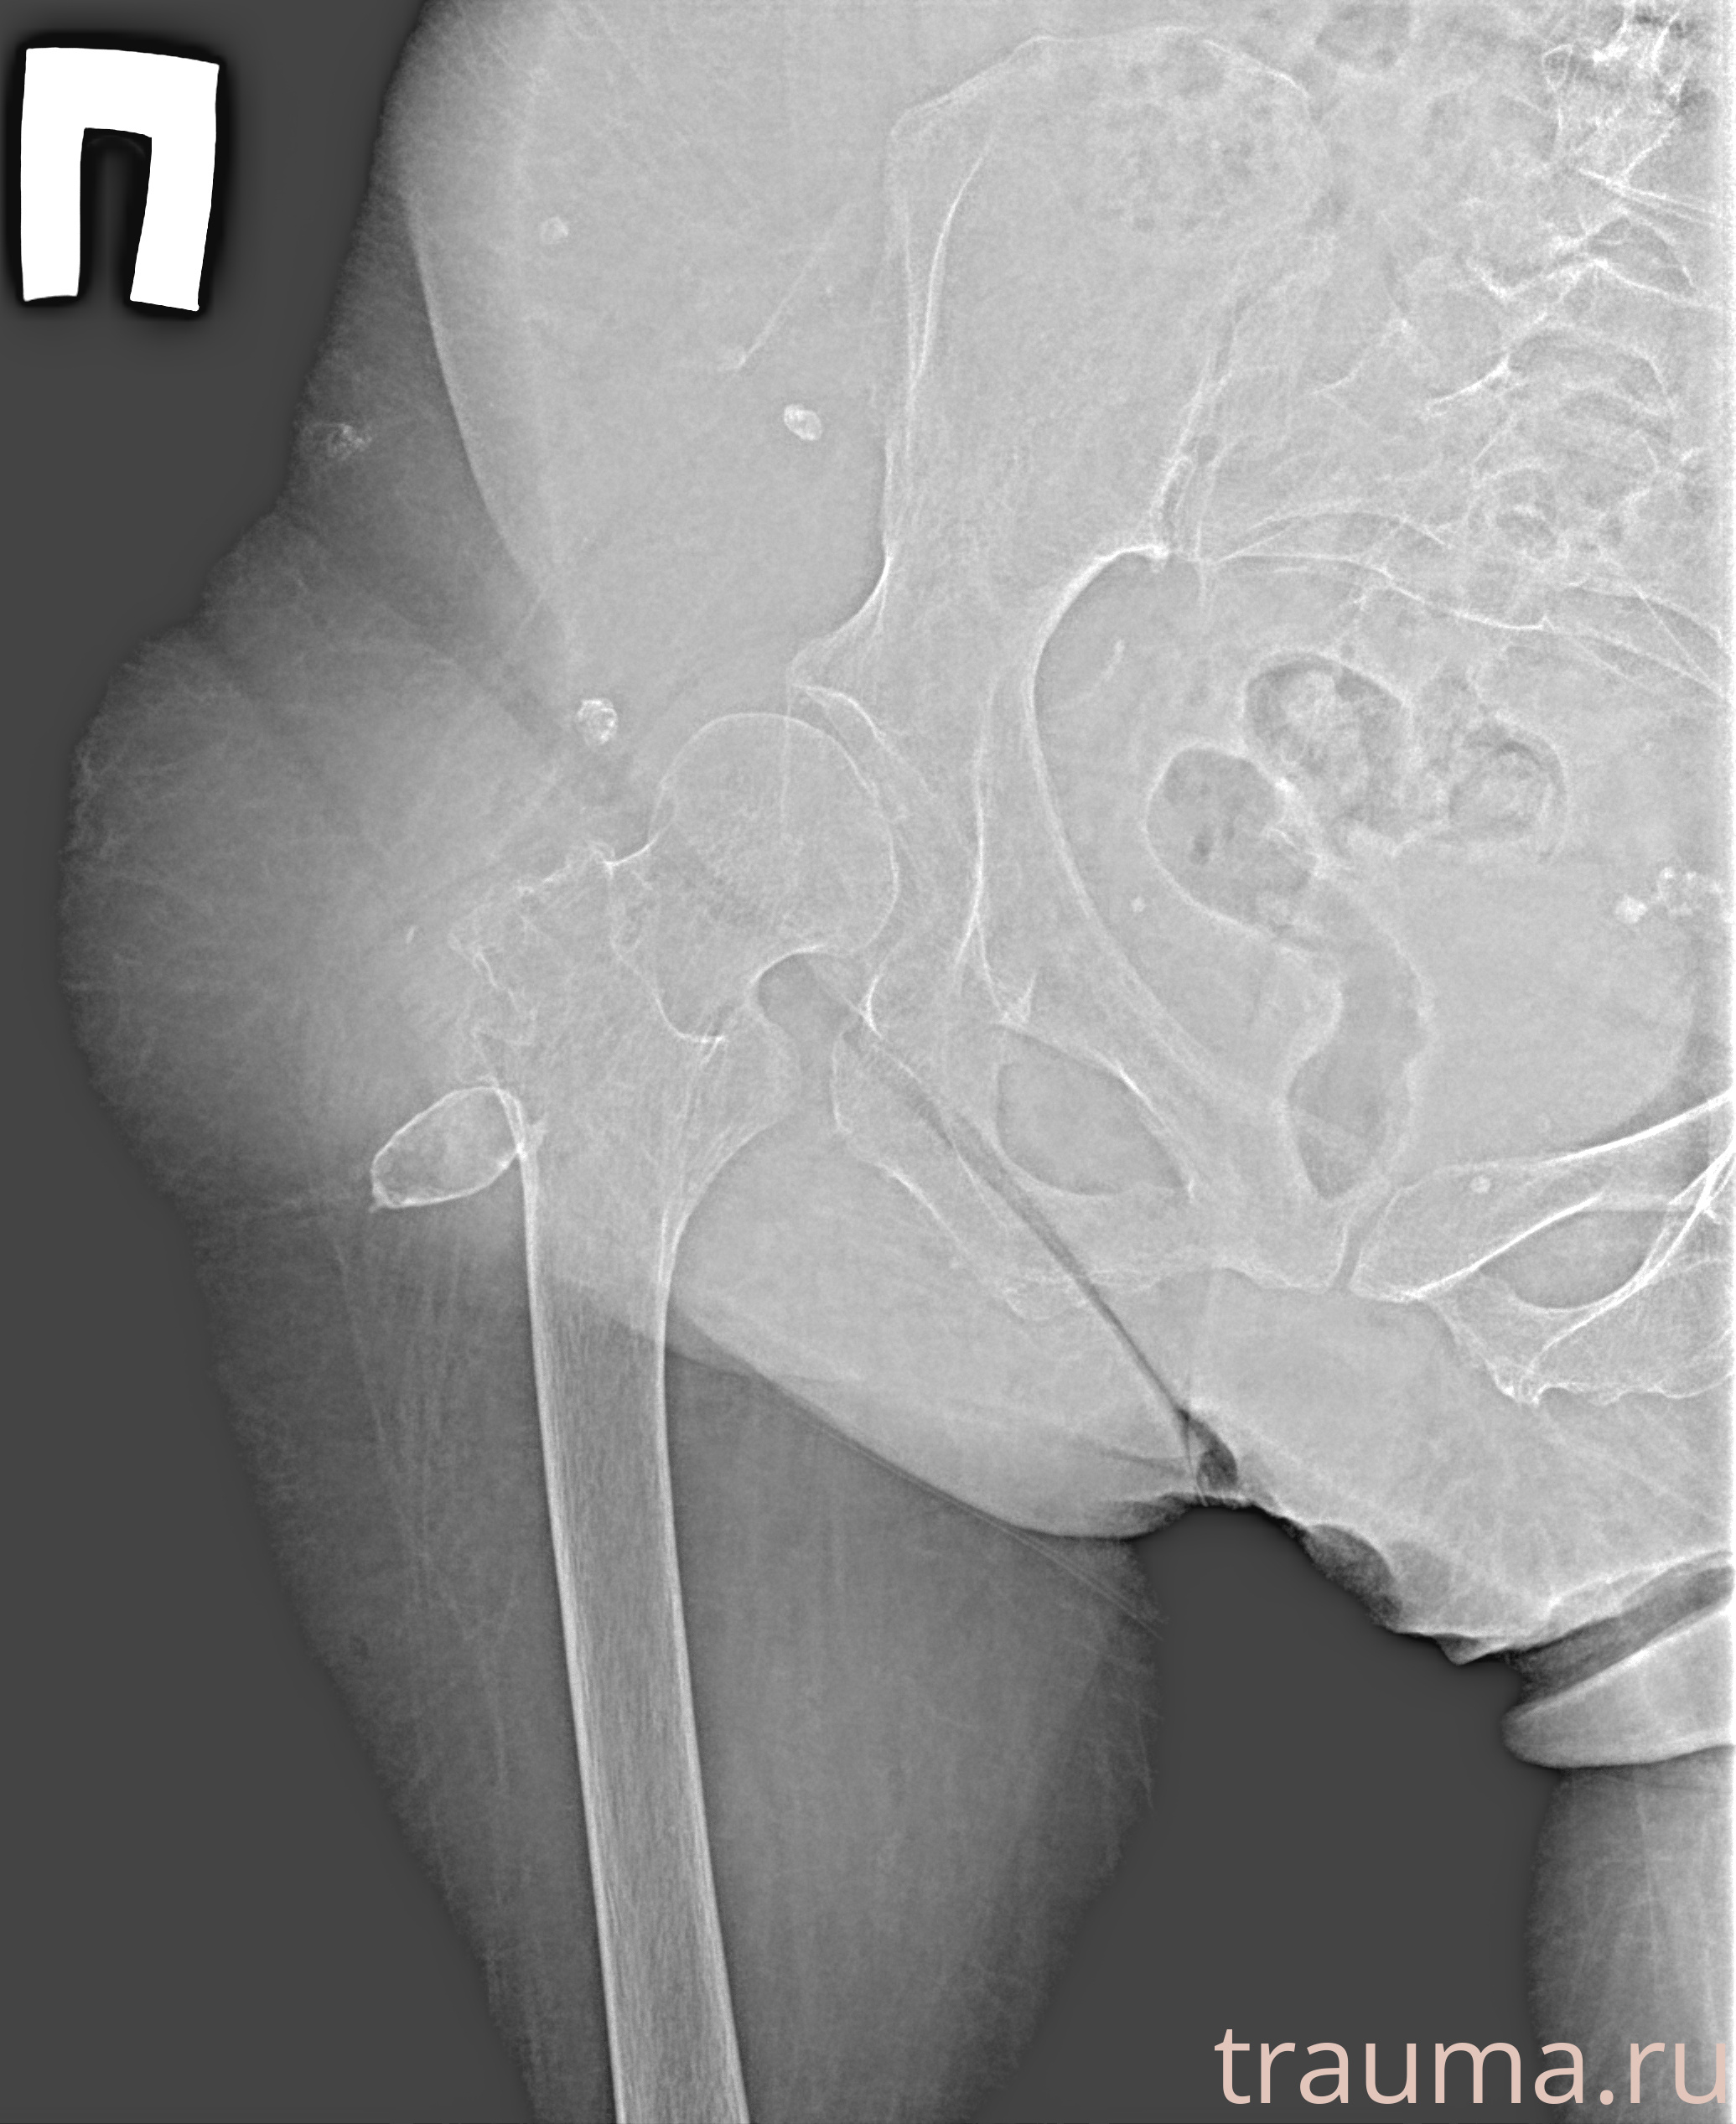

Рентген на дому: по вашему адресу приезжает врач-рентгенолог, травматолог-ортопед с мобильным рентгеновским аппаратом, проводит диагностику травмы или заболевания, делает необходимые рентгенограммы, дает рекомендации по дальнейшему лечению. Получить качественные снимки в домашних условиях возможно благодаря уникальной методике, разработанной МосРентген Центром для института  Склифосовского